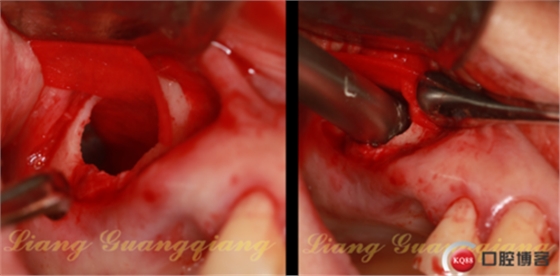

一次性注射器,連接50ml注射器上的針頭,輕輕刺入囊腫外側(cè)壁,緩慢吸出里面的液體。

這是什么?盡量尺寸大的生物膜,修剪成這種形態(tài),置于生理鹽水中浸泡。

膜收腰的狹窄區(qū)剛好卡在洞口,大部分的膜被平攤在上頜竇膜下方:1,防止殘余的囊液污染骨粉。2.防止大顆粒的骨粉刺傷上頜竇膜。下方植入骨粉。